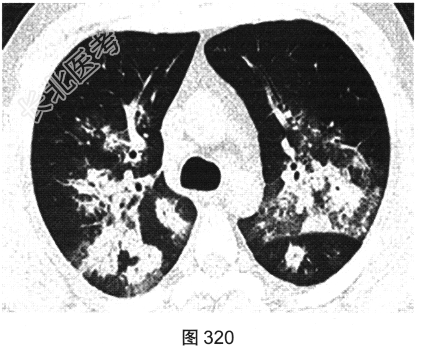

- [材料题] 患者男性,30岁,发作性咳喘3年,吸入冷空气后鼻塞、流黄白色脓涕,外院予环丙沙星治疗后症状缓解,其后鼻塞,夜间睡眠中喘憋反复发作;咯血、发热1周,以傍晚和夜间为著,体温最高为38.5℃,伴畏寒及周身疼痛,痰中带血,为鲜红色,伴胸痛、咳嗽,喘憋明显。胸部CT检查如图319~图324所示。

- 多项选择题1.在提供的CT平扫图像上,可观察到下列哪些影像学征象( )

A、晕征

B、双肺结节影

C、小叶间隔增厚

D、反晕征

E、小叶中心结节

F、双肺磨玻璃影、斑片实变影

G、支气管壁增厚、管腔扩张、支气管充气征